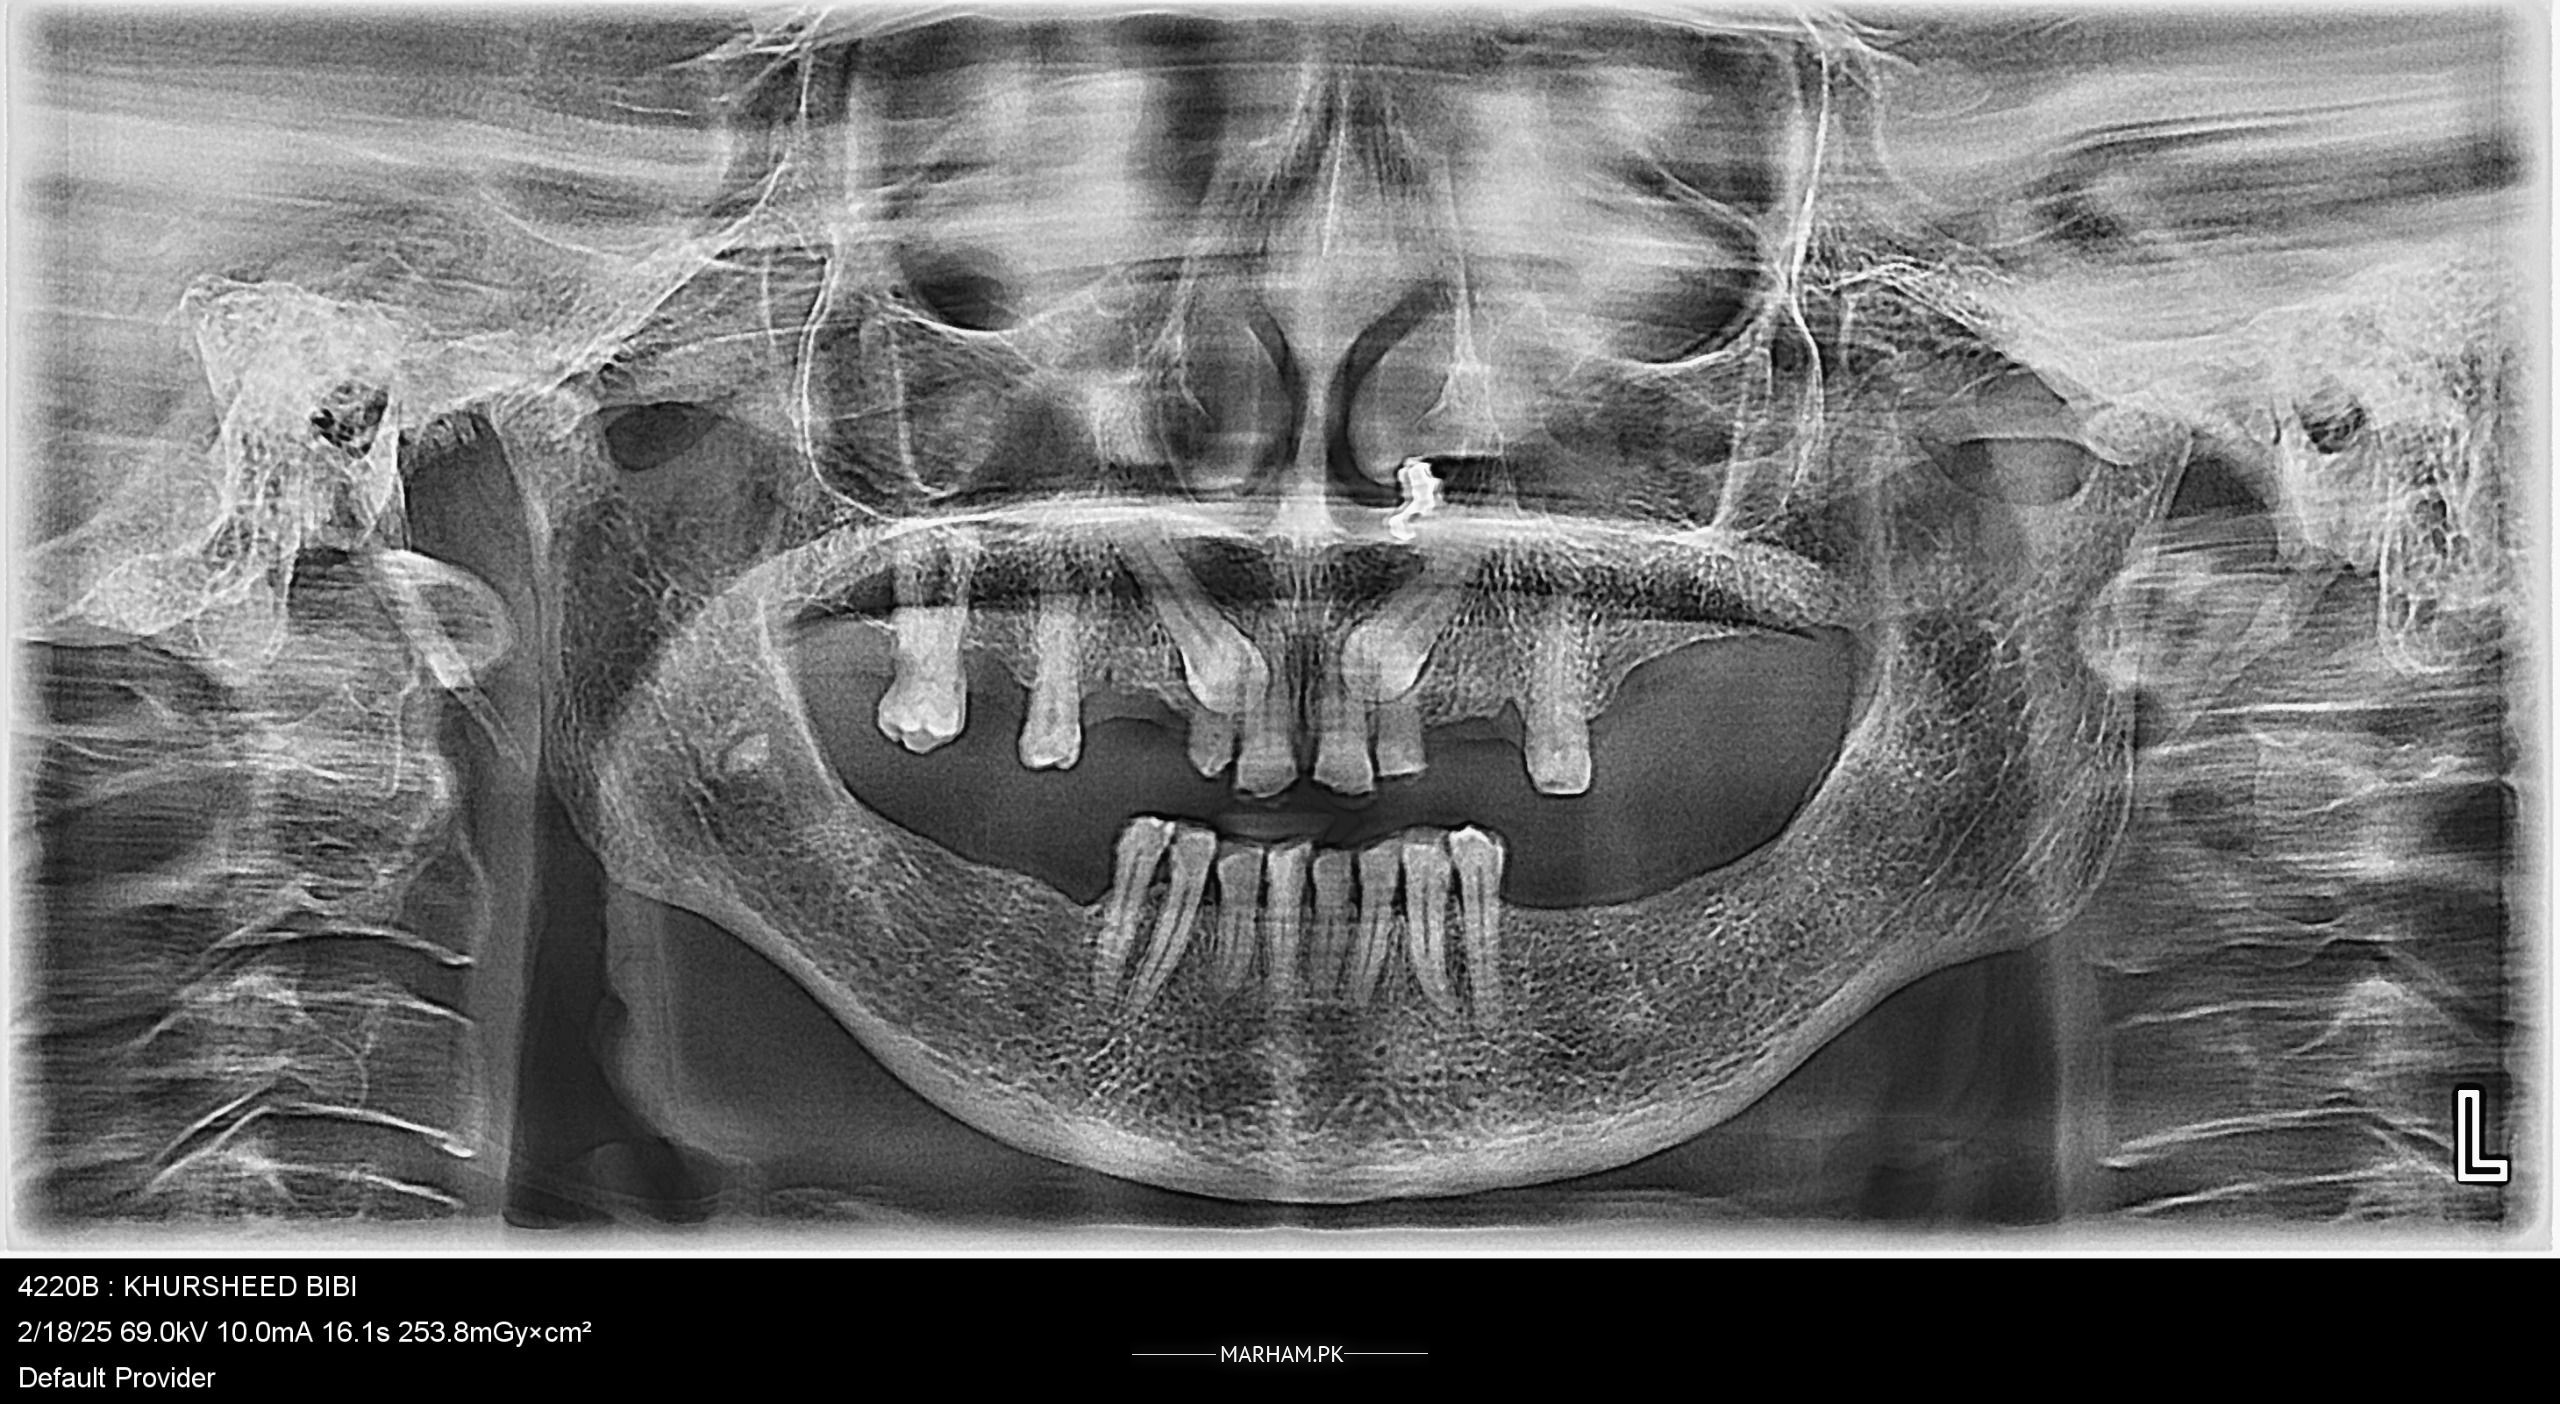

asalamalaikum ma apni mama ko dentist k pas la k gay tha unho na btaya k upar wali arch mukamal nae lag sakti kiu k in k 2 dant hadi ma phasy huy Hain or jab hum dant lagain ga to pain ho ga in ko.to mujy baqi dental doctors sa suggestion chaiay k kia hum inhy upar fix dant laga dain ya utrny charny waly lagwain kiu k 2 doc na kaha nae lagny fox 2 na kaha lag Jain ga koi problem nae ho ga so getting confused k kia krna chaiay need openion plz

implant can do ..but it can b confirmed by cbct scan ...othrwise removable is the best option ...baki age kya hy inki ?

According to the radiograph shared, fixed partial denture can definitely be given and if the patient doesn’t have any medical issues like uncontrolled diabetes, implants can also be placed. Still examination and clinical evaluation will be required. A consultation must be sought with a Marham verified restorative specialist in your area for proper diagnosis and treatment planning. Follow @tareensdental for more oral and dental health related tips.

Fixed lgwanay hain to yeh dant nikalwanay hongy. Fixed denture bone density py depend krta hai jo is xray main itni achi ni lgri lekin bone density confirm krny k liye CBCT ki zroort hai is xray sy ni idea lgaya jaskta. If you want to go for removable ones to nikalny ki zroort ni hai in danton ko

walaikumaslam..its better to have removable teeth in both jaws that is the safest option ....if we try fixed teeth like implant, that is not possible , but someone may try bridge but that cannot be a long lasting option and involved cutting of teeth.so solution is removable partial dentures both upper and lower .thankyou

Wa alaikum Salam

first thing I need to know about medical history of your mom. if she is not suffering from any medical condition, my suggestion is to go with upper fixed bridge after doing RCTs of upper front teeth and lower removable denture or if want fixed, two implants on both sides for fixed. I'm the specialist for putting new teeth. ideally you should get it done from prosthodontist